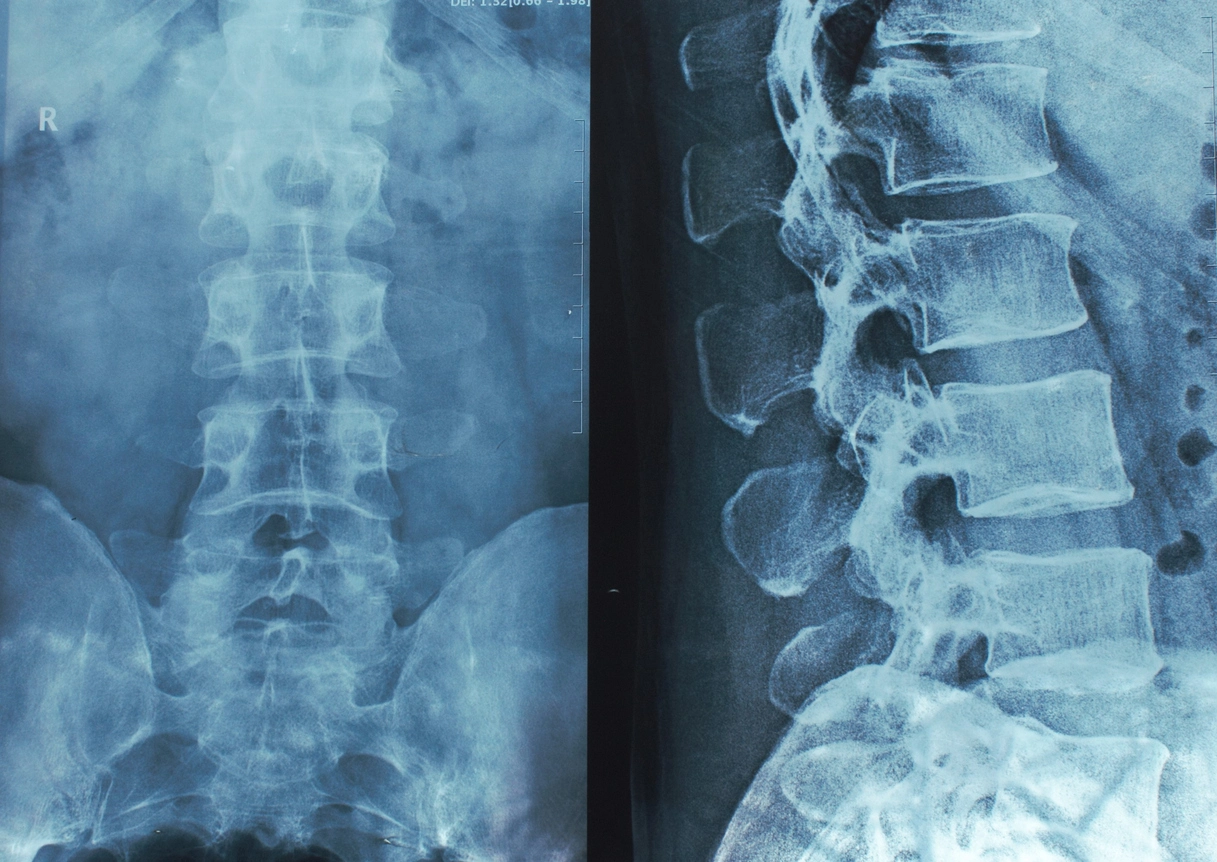

A spinal cord injury can change your life in an instant, leaving you with lasting or even permanent paralysis and overwhelming physical, emotional, and financial challenges. About 18,000 spinal cord injuries happen in the U.S. each year — and victims of truck crashes, oilfield accidents, and industrial workplace incidents face the highest risk of serious complications, including paralysis and lifelong disability.

Spinal cord injuries can happen in an instant, and the consequences are life-altering. Data from the National Spinal Cord Injury Statistical Center (NSCISC) shows that motor vehicle crashes and falls are the top two causes of spinal cord injuries nationwide, accidents that occur all too often in Texas oilfields, refineries, and roadways:

A spinal cord injury (SCI) can change your life in an instant. The spinal cord is a bundle of nerves running from your brain down your back, carrying messages that control movement, sensation, and vital bodily functions. When it’s damaged —through a fall, motor vehicle crash, or workplace injury — it can result in temporary or permanent paralysis, loss of feeling, or other serious complications.

In some cases, CT scans may not reveal the full extent of a spinal cord injury. Even if initial imaging seems minor, symptoms can worsen over time. That’s why it’s critical to follow up with medical specialists and contact an experienced spinal injury lawyer if you suspect your injuries are more serious than medical professionals initially report.

- Get medical care immediately: Even if symptoms seem minor, an SCI can worsen quickly. Prompt evaluation and imaging (MRI, CT scan, X-rays) are critical.